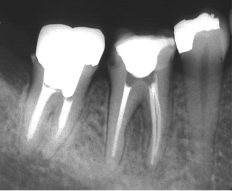

とりあえず痛む部位を、レントゲン撮影をさせて頂きました。

そのレントゲンをみてびっくり!(◎_◎;)

痛いと言われる歯の部分だけ歯を支えてる骨が溶けていましたΣ(゚д゚lll)

レントゲンを診ると、歯の神経に細菌感染が由来した病変から、歯周組織にまで波及した結果であることが認められたため、まずは歯の神経の治療を優先し、歯周治療と並行して治療を始めました。

この歯を支えている骨は見事に回復しました )^o^(